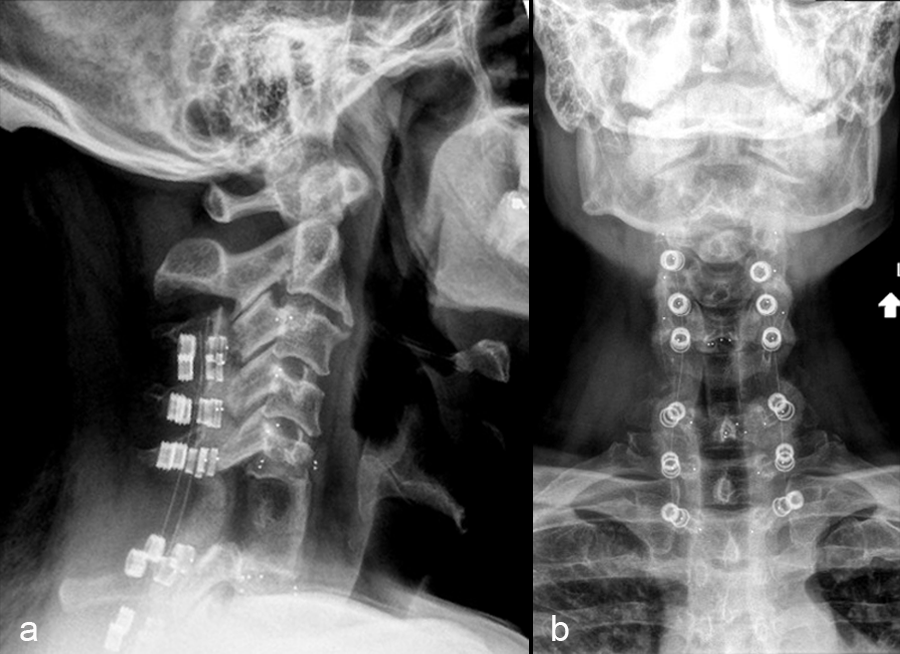

The patient underwent a CT guided biopsy that demonstrated a brachyury positive lesion consistent with a chordoma versus benign notochordal tumor. He underwent a two-stage operation for en bloc resection of the lesion. Cervical spine stabilization was achieved using CMORE® Carbon/PEEK implants. The radiolucent nature of these implants permits artifact-free postoperative imaging and more precise radiation treatment, an important consideration in patients with spinal tumors.

The first stage was a posterior approach with a C3-T3 instrumented fusion using CMORE® Carbon/PEEK lateral mass and pedicle screws (Fig 2) with resection of the posterior elements of C6, mobilization of the C6 and C7 nerve roots and vertebral arteries bilaterally. The second stage was a left sided anterior cervical approach with completion of the C6 spondylectomy and en bloc resection of the C6 lesion. The resected lesion tissue is shown in Fig 3.

The anterior cervical spine was reconstructed from C5-C7 using tricortical iliac crest autograft and an icotec Carbon/PEEK anterior cervical plate system (Fig 4). Following reconstruction, imaging (Fig 5) demonstrated no MRI artifact in the sagittal (a,c) and axial (b,d) planes.